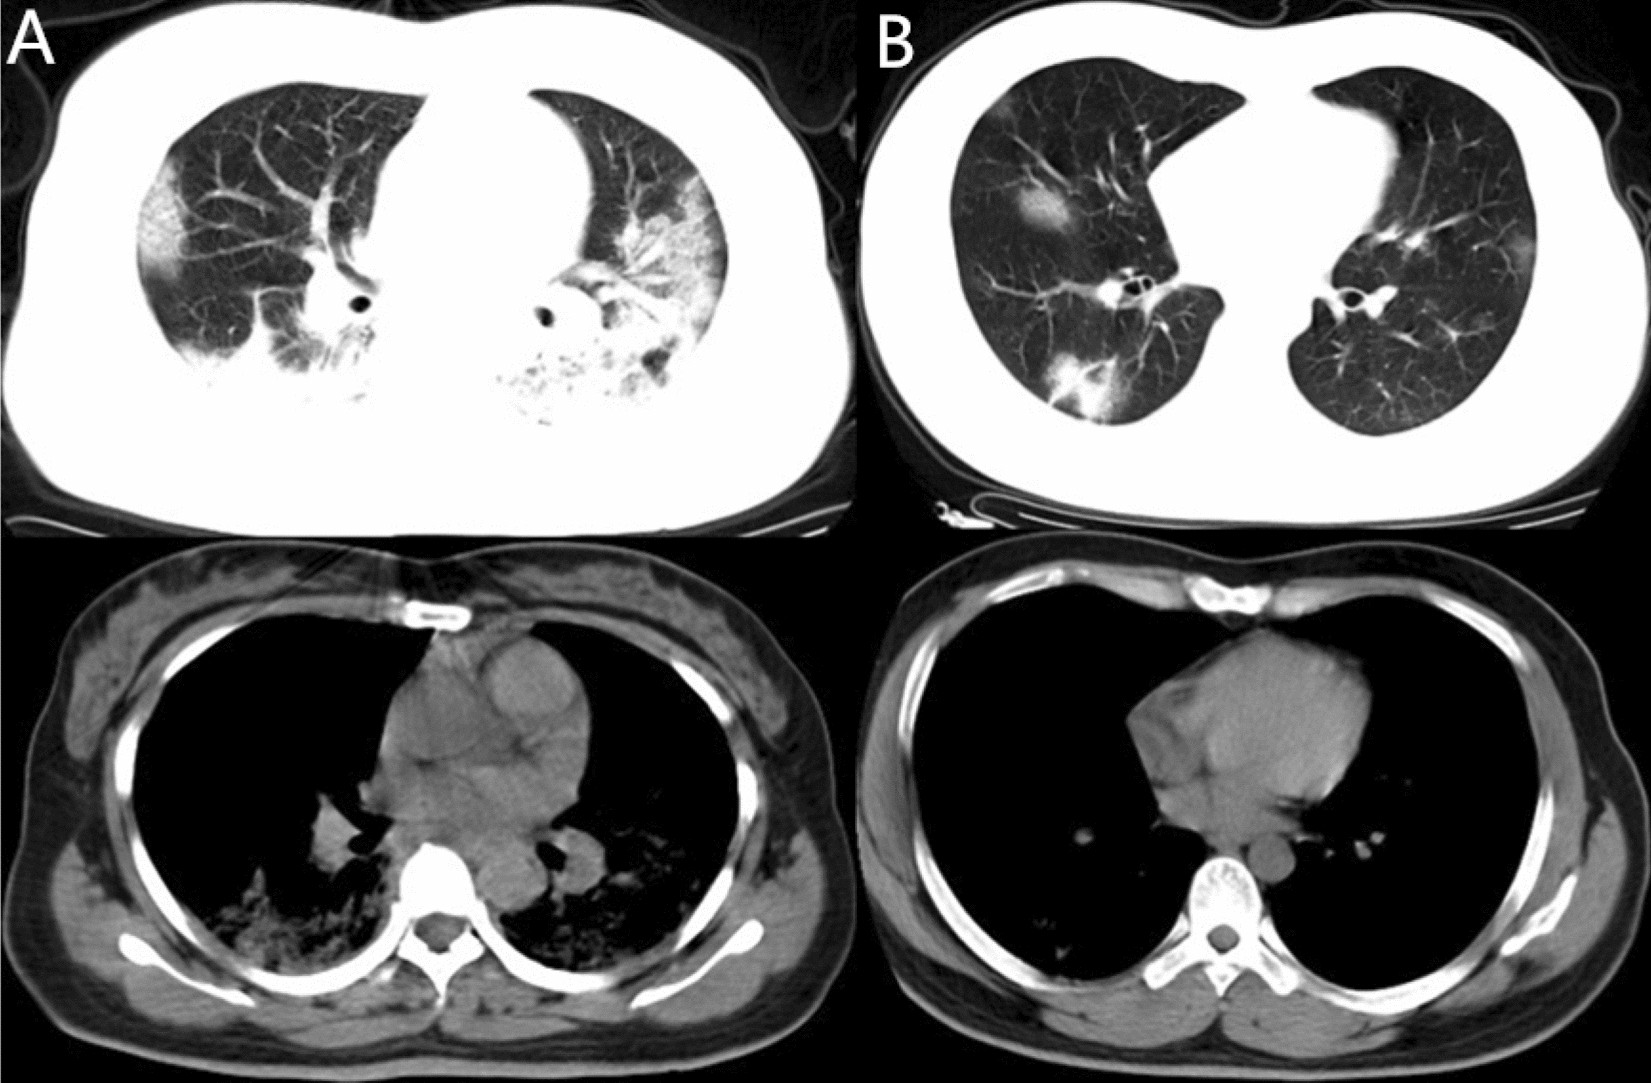

Figure 5

Example of patients with CT demonstrated as consolidation > GGO component in Group 2. (A) 29-year-old female confirmed with COVID-19 pneumonia in Group 2 who had hospitalization days of 19 days. CT images demonstrated multiple lesions with mixed density which were predominantly solid components (arrows). (B) 28-year-old male in Group 2 with hospitalization days of 19 days. CT images also demonstrated multiple mixed density lesions with predominantly solid components (arrows).